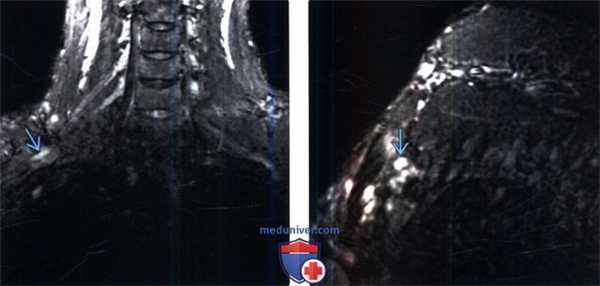

(Слева) На фронтальном STIR МР-И (правосторонний неврологический СВАГК) отмечается патологическое усиление интенсивности Т2-сигнала элементов верхнего ствола плечевого сплетения в пределах ВА.

(Справа) На косо-сагиттальном STIR МР-И отмечается локальная гиперинтенсивность Т2-сигнала верхнего ствола плечевого сплетения, соответствующая клинической симптоматике правостороннего неврологического СВАГК.